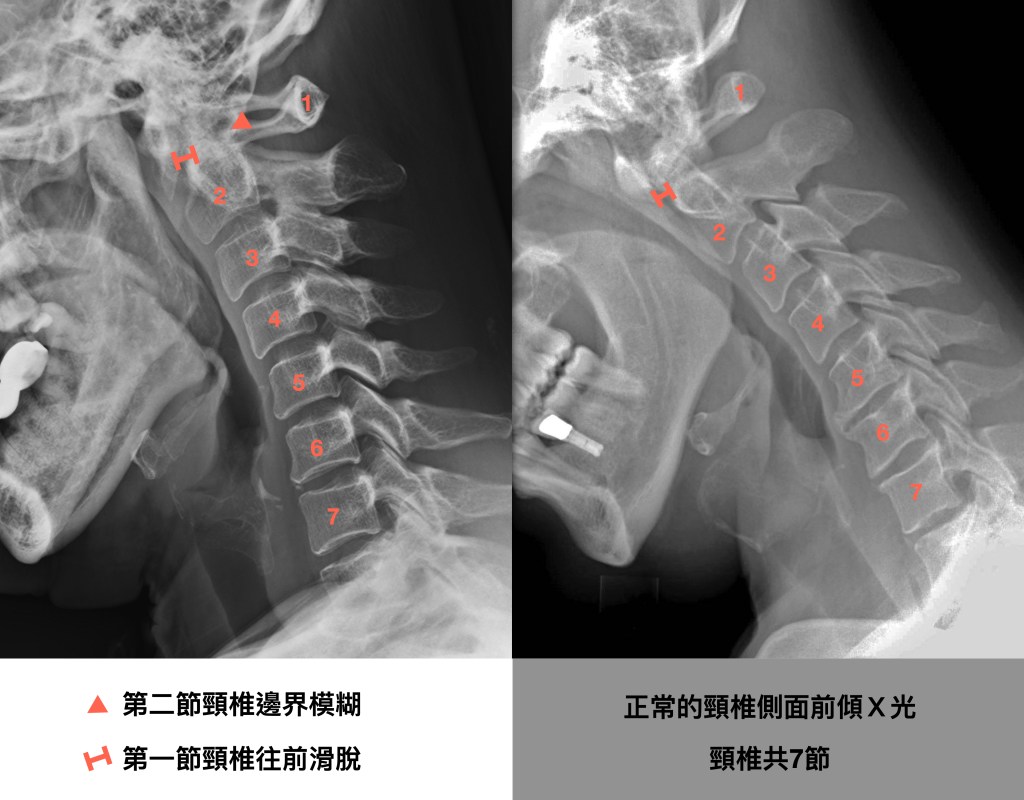

圖上的左手邊是阿姨的脖子,右邊是正常的範例。

阿姨的頸椎第一節與第二節間的關節有發炎且侵蝕的病變,造成長期慢性的後頸高位疼痛,低頭看下方的時候會加劇疼痛症狀。雖然在磁振造影MRI上並未看到第一節頸椎因為滑脫而壓迫到脊髓神經的情況,但未妥善治療下可能讓頸椎滑脫情形惡化。

侵蝕頸椎第一二節之間的關節後,會造成第一節頸椎滑脫,典型的症狀是病人在脖子往前傾,低頭往下看的時候會後頸痛。也有滿多人是很難描述特別哪個姿勢才會脖子痛,反正就是在脖子高位的地方會痛。

嚴重滑脫的話,第一節頸椎在低頭時往前滑會壓迫到頸椎內的脊髓,嚴重的脊髓神經壓迫可能引起從頸部以下癱瘓。